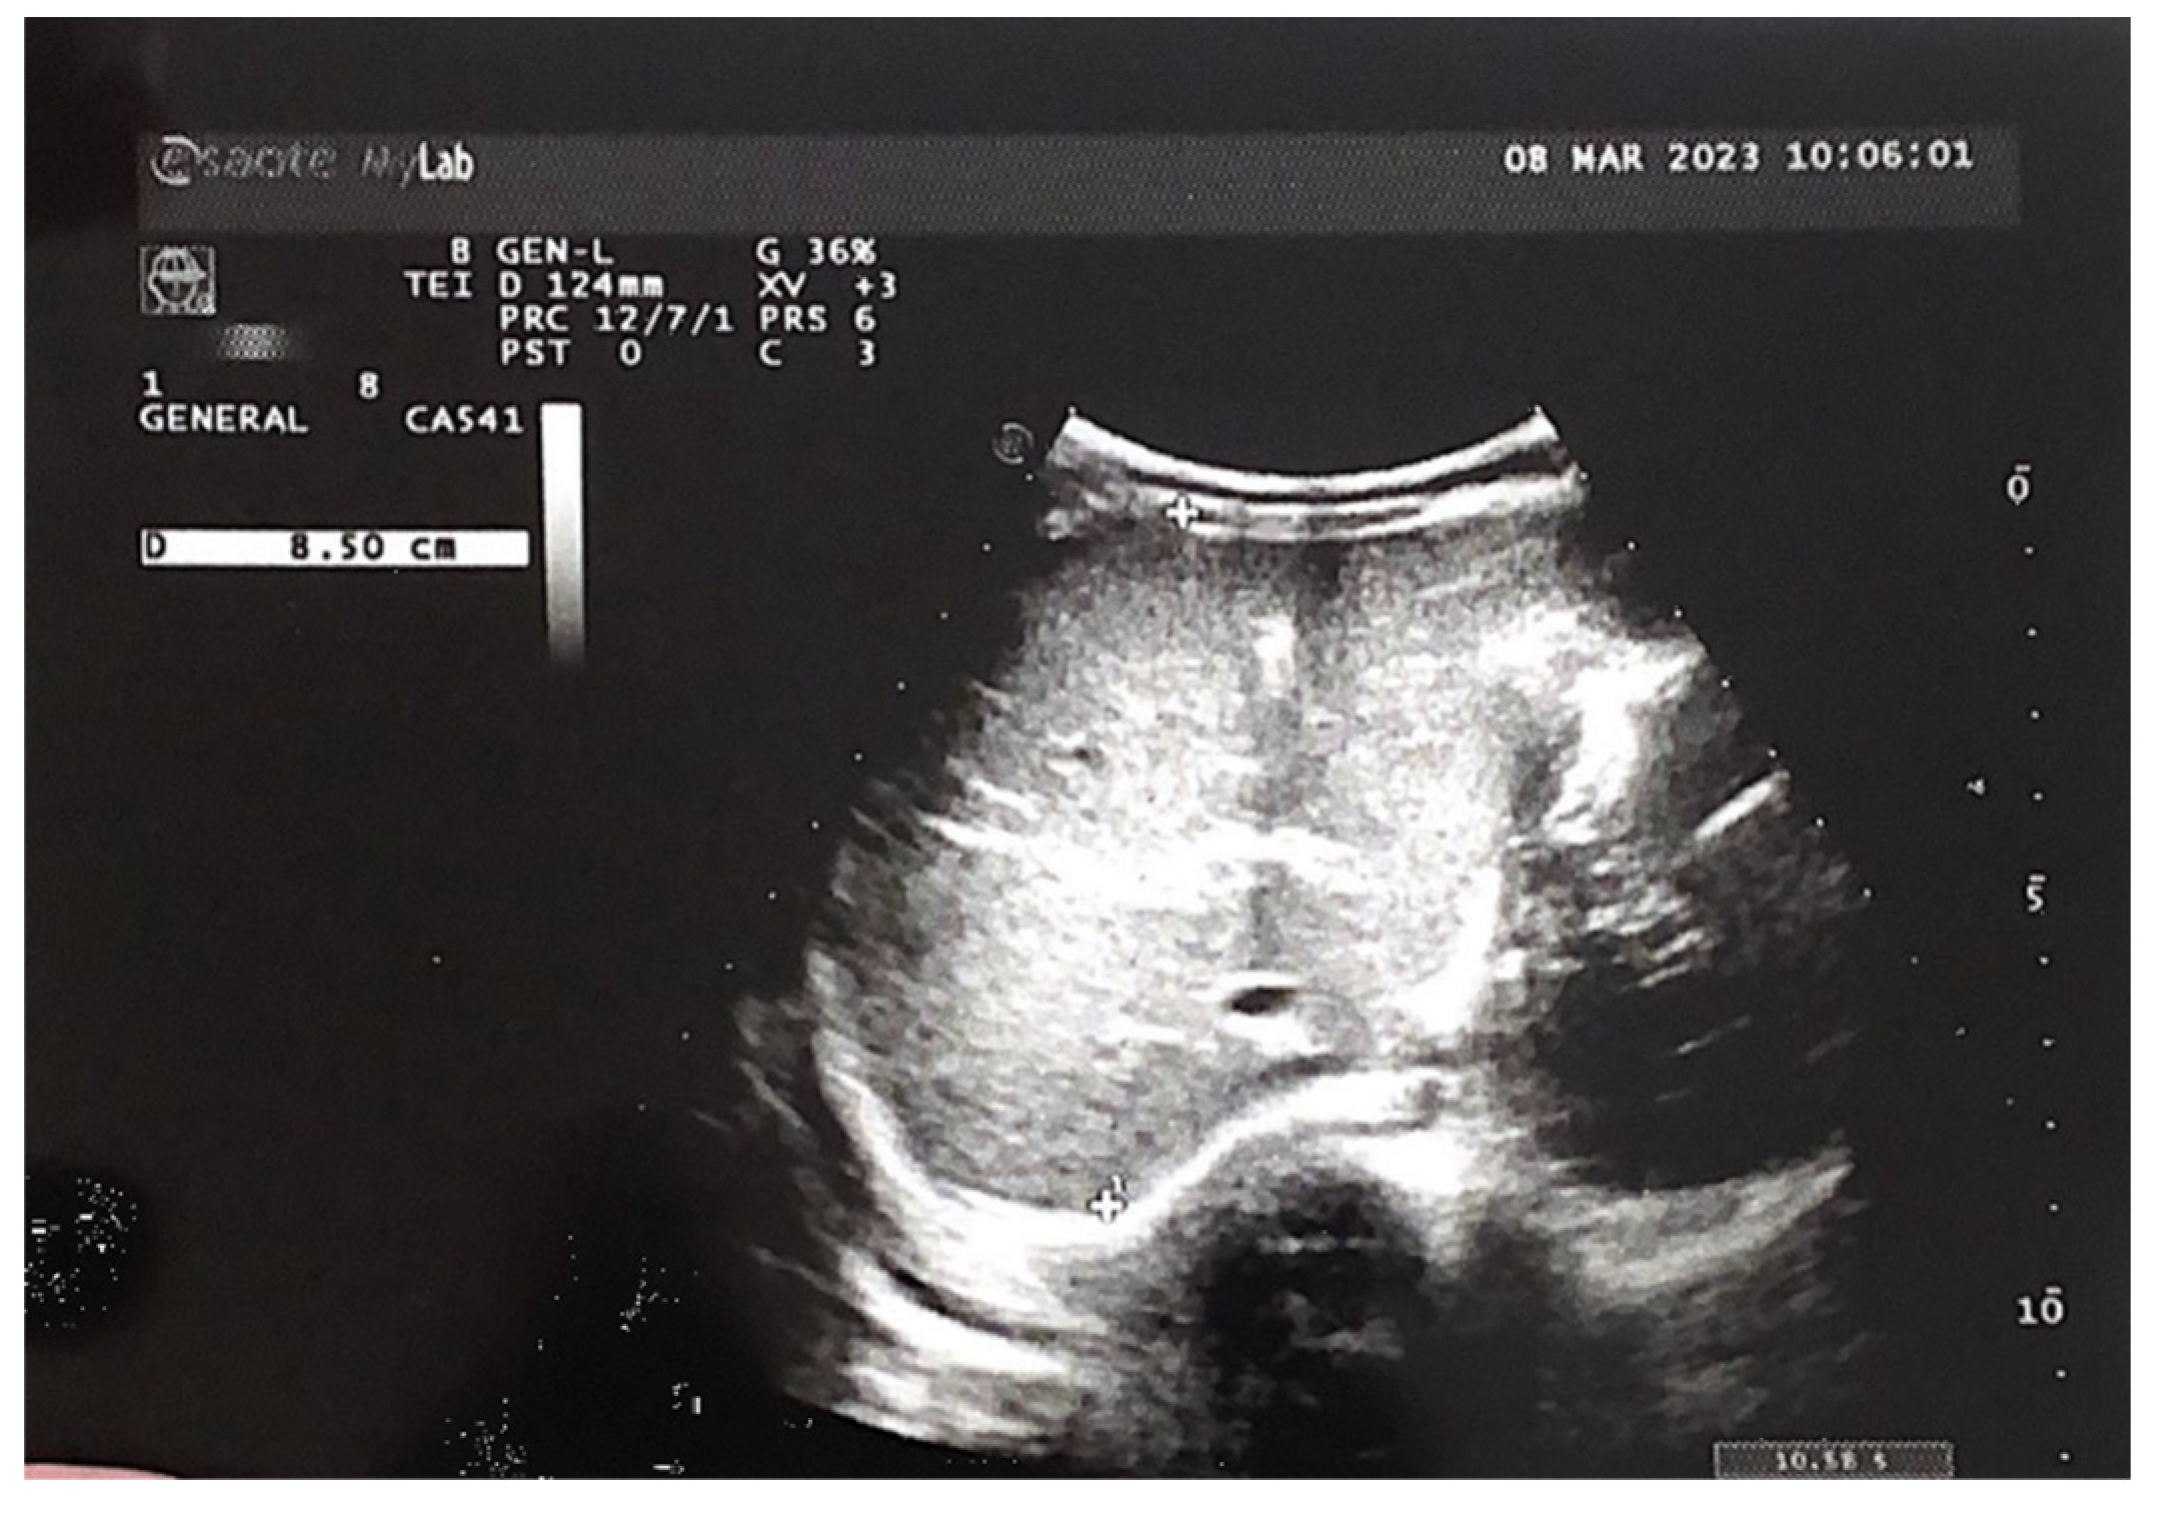

Figure 7. Almost complete regression of the hepatic hemangiomas.

Preprints 73814 g006

Figure 8. A circular hypoechoic lesion, located in segment VI.

Preprints 73814 g007

An abdominal ultrasound examination, performed during a neonatal and surgical consultation at the 9th month of life, showed almost complete regression of the hepatic hemangiomas (see Figure 7). A liver with homogeneous parenchymal echogenicity was observed, with the exception of a circular hypoechoic lesion, located in segment VI, its diameter being 9 mm (see Figure 8). The liver size in the midclavicular line was 77 mm.